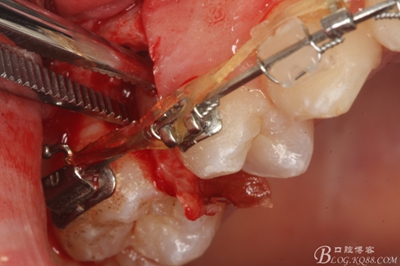

圖14.用小球鉆縱分15牙根

圖15 .微創(chuàng)挺把15牙根縱分成近遠(yuǎn)中兩塊

圖16.微創(chuàng)挺挺松近中根面部分,從16與14之間間隙出來